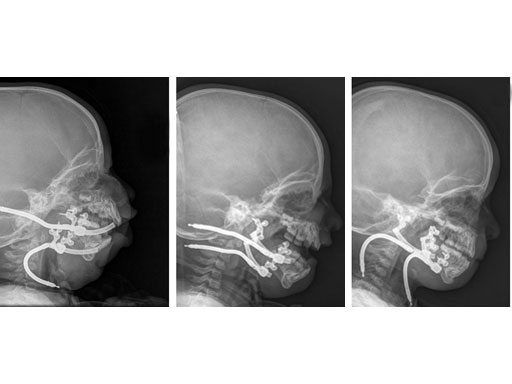

Multiplanar mandibular with curvilinear distractor in a 16-month old girl with Treacher Collins syndrome to improve mandibular and airway morphology and achieve tracheostomy removal.

Fig 2 ac Lateral facial x-rays. Left to right: Immediately after distractor placement; During distraction; At completion of distraction.